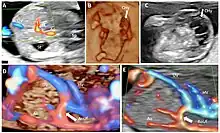

Absence of the portal system in a first trimester case associated with hygroma and aorto-umbilical fistula. (A): Transverse plane of the upper abdomen with color Doppler applied, showing umbilical cord insertion, stomach, the prominent hepatic artery and no afferent liver venous perfusion; (B): midsagittal plane reconstructed from a three-dimensional volume acquisition were the crown-rump length is measured and fetal cystic hygroma can be observed (white arrow); (C): transverse sonographic view of the neck showing the septated nuchal cystic mass (white arrow); (D): 4D STIC showing in the longitudinal view of the fetal abdomen an abnormal connection (white arrow) between umbilical vein and aorta. (E): same aspects as (D), using two dimensional color Doppler assessment. UV umbilical vein, HA hepatic artery, Ao aorta, St stomach, Sp spine, CHy cystic hygroma, AoUf aorto-umbilical fistula.